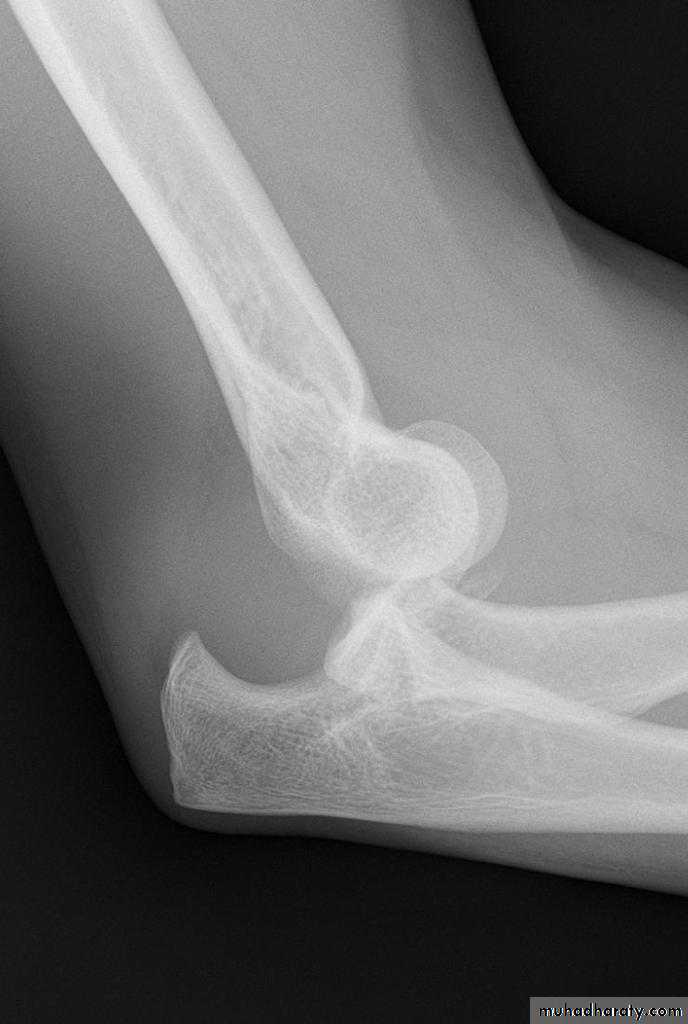

X-ray;

To establish the diagnosis and exclude associated fractures.